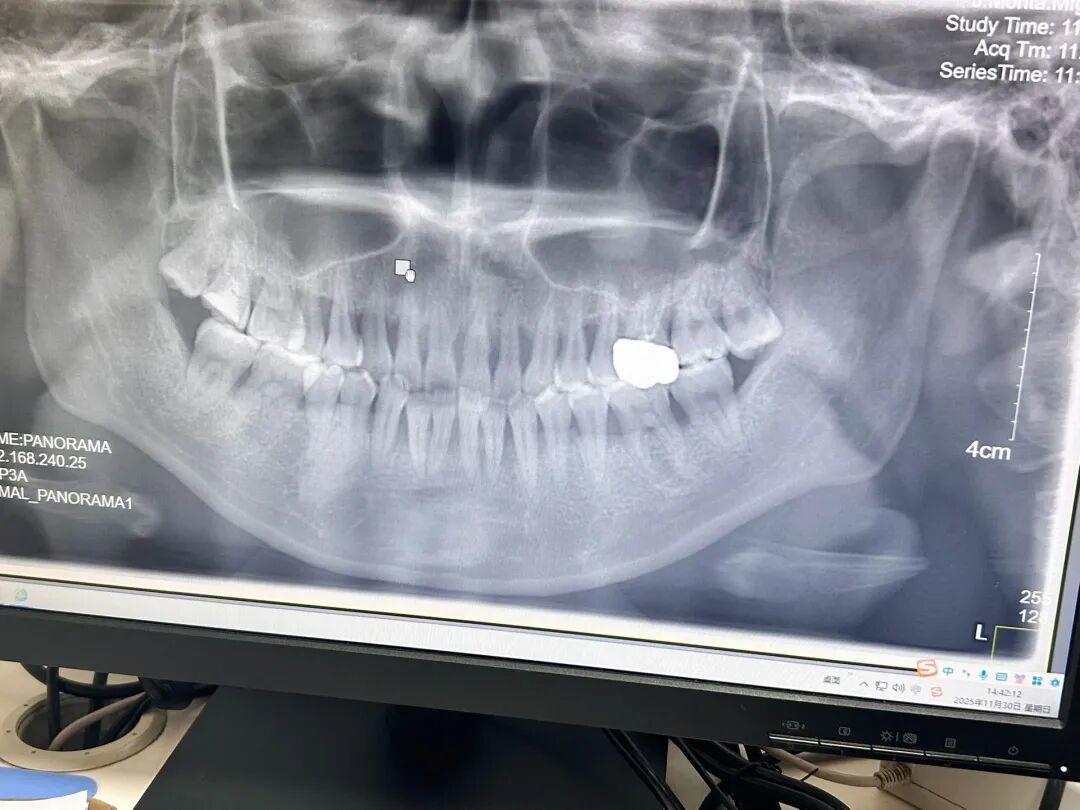

2025年11月,赵玥于武汉市一家三甲牙齿专科病院拍摄的牙片 图/受访者提供

赵玥本年27岁,她的牙周病史则能追猜度大学时期。那时,她一刹发现刷牙时牙龈会出血,但对牙周病了解甚少,仅仅浅近去病院按期洗牙。赵玥地方城市不发扬,大夫未说起牙周病问题,加之洗牙后出血的症状照实舒服了,以为算是好转,但其实病程并未中断。旧年在武汉就医时,她已有一颗牙酸痛、微弱飘浮,被确诊为重度牙周病,测量出牙周袋深度达7—10毫米。